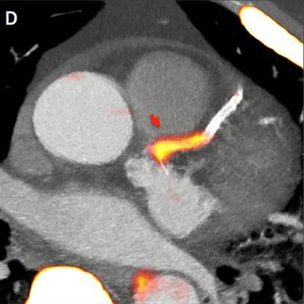

The researchers used a radioactive tracer which can seek out active and dangerous plaques. This was combined with high resolution images of the heart and blood vessels.

The overall effect is a detailed picture of the heart with the danger zones clearly highlighted. The technology is already used to detect tumours in cancer patients.

The scan highlighted the plaque which caused the heart attack in 37 of the patients according to a study published in the Lancet medical journal.